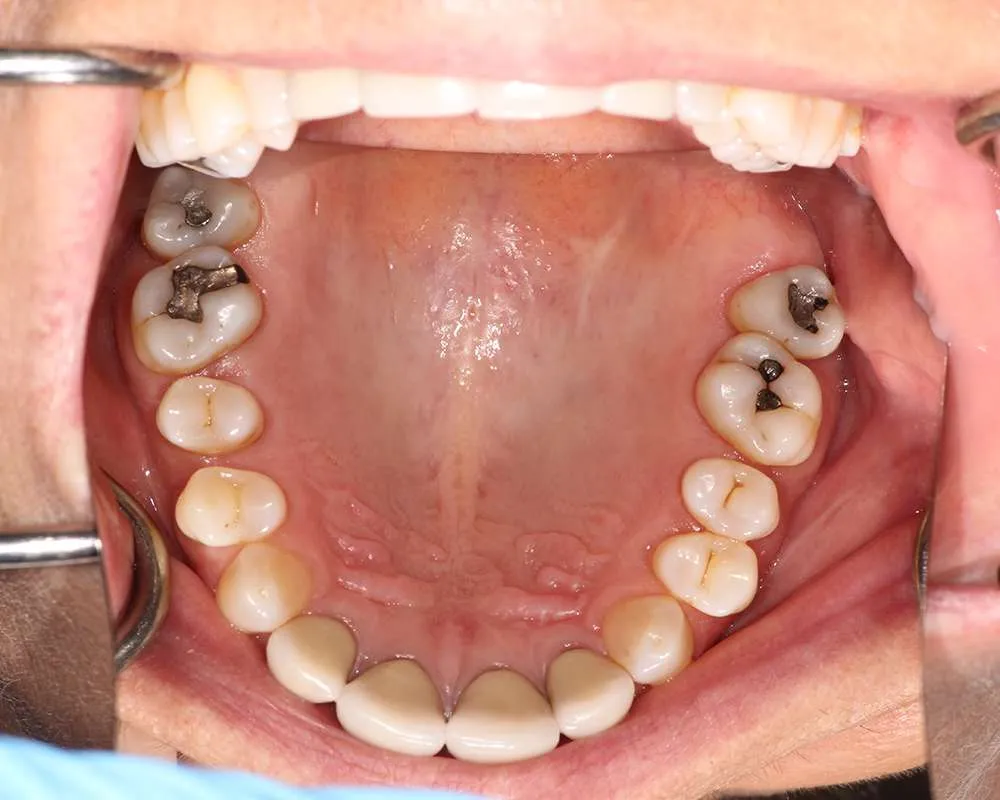

Real Stories, Real Results: Case Studies Showcasing How Our Personalized Approach Transforms Smiles and Lives

Witness the Remarkable Changes We Can Achieve

The safe removal of mercury fillings is crucial for your health and well-being. At our practice, we follow strict protocols to ensure that mercury amalgam fillings are removed safely and effectively.